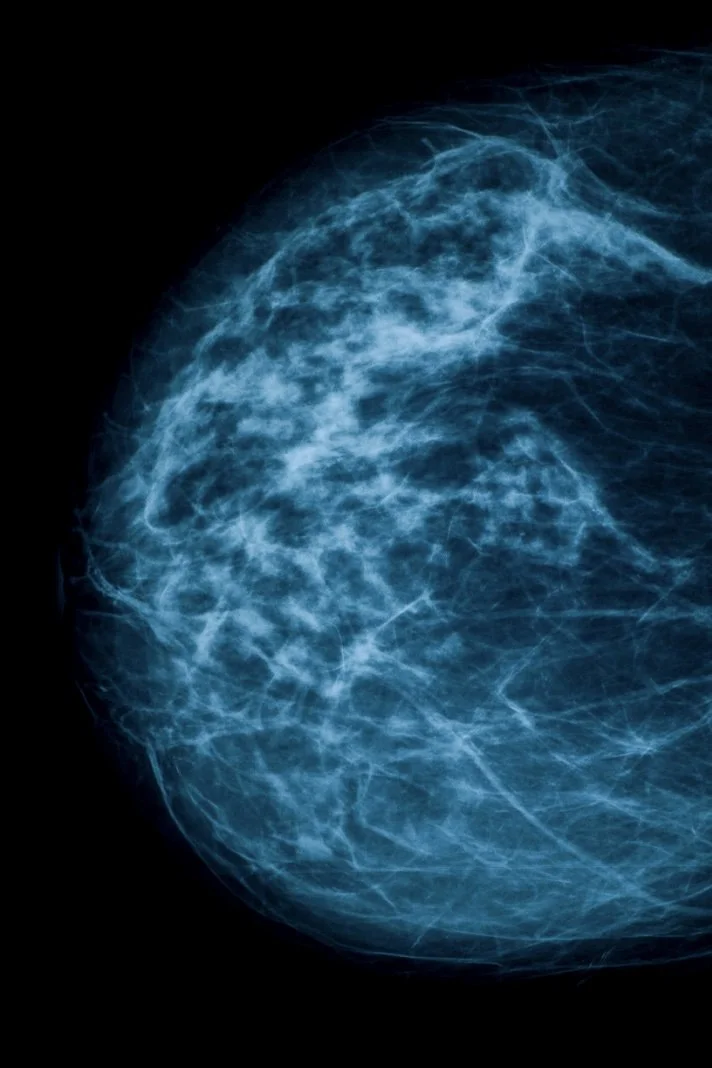

The problem is that for 50% or more women with dense breasts, this is not sufficient for early breast cancer detection and there is no mandate that more sensitive screening tools be covered by insurance to assure early cancers are not missed in these women. Mammograms are great for detecting calcified lesions and modalities such as breast MRI (magnetic resonance imaging) and US (ultrasound) are much better at detecting soft masses (in combination with mammography the sensitivity can be 100%). For women with dense breasts some radiologists liken trying to find cancer on a mammogram as “trying to find a snowball in a snowstorm.” Because glandular tissue that has yet to turn to fat shows up as white on mammograms (the same color as cancer) mammograms will not be evaluable in 40-50% of breast tissue. In 2023, the FDA published a rule stating that mammogram reports sent to patients must include breast density, which would be described as either “not dense” or “dense” which took affect on September 10, 2024. However, once informed of this, there are no further recommendations or mandates to cover screening for these women. Essentially, they receive a letter saying “your mammogram looks negative but you have dense breasts so we’re not sure it's negative. We’ll try again next year.” There is a rising number of women with “normal mammograms” within this context that ultimately are diagnosed with advanced breast cancer.

In reality, these women should subsequently undergo either breast MRI or breast US to increase the sensitivity of early breast cancer detection but there is no requirement to do so. Some radiologists will recommend additional screening and many will not comment beyond the breast density. There is no standard. The USPSTF states that they can’t make additional recommendations on any additional testing without evidence because there are no randomized controlled trials showing MRI will save more lives even though The American College of Radiology supports MRI as the preferred test for women with dense breasts and breast radiologist strongly express that it will save lives. Without randomized controlled trials, the USPSTF will not make recommendations and without USPSTF recommendations, insurance companies won’t approve coverage. For the majority of women who are not informed by the health care system of what screening they should actually undergo and who are unable to pay out of pocket for it, medicine, and to a greater extent the insurance companies, are failing women at risk for missed early detection of breast cancer and imposing a higher mortality if diagnosed at a later stage. Even with new technology and studies in the works, it will still take years to materialize in to USPSTF recommendations leaving women vulnerable to late stage diagnosis of breast cancer that we have every possibility of preventing. Dr. Daniel Kopans, professor emeritus of breast radiology at Harvard’s Massachusetts General Hospital stated that “ If we did MRI as the routine screening for everyone, we probably would save [almost] everyone from breast cancer.”